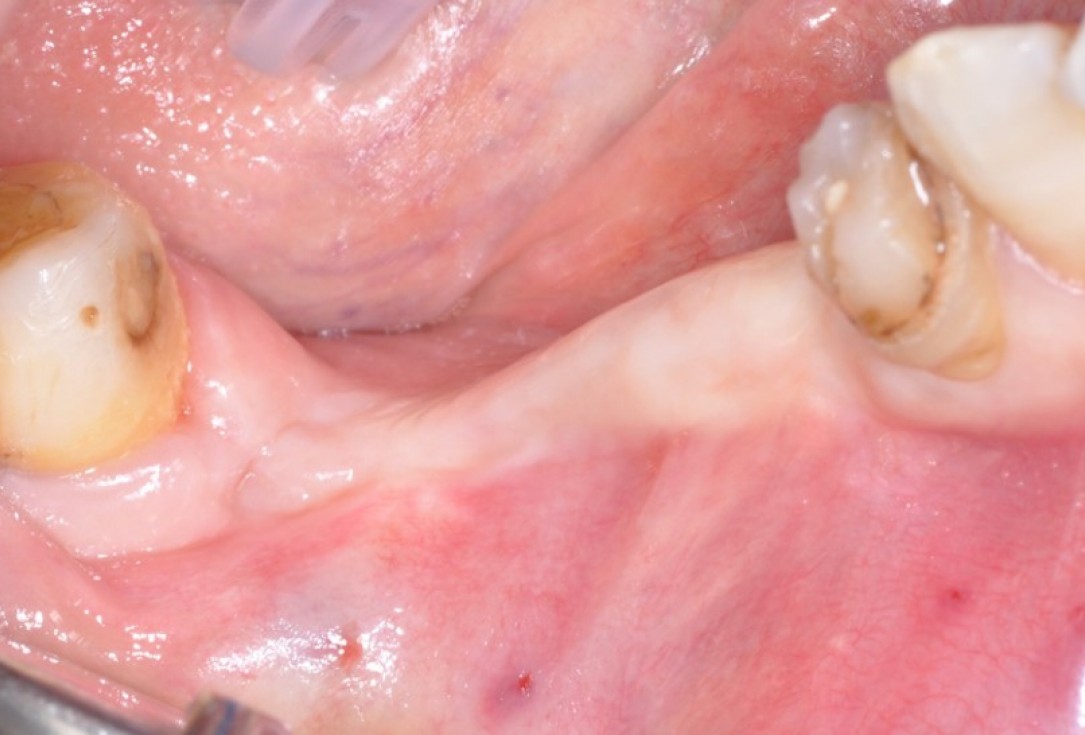

2/9 - Lost ridge bone and keratinized tissue after tooth extractionPeri-implant soft tissue augmentation for pontic with mucoderm® - Dr. M. Frosecchi